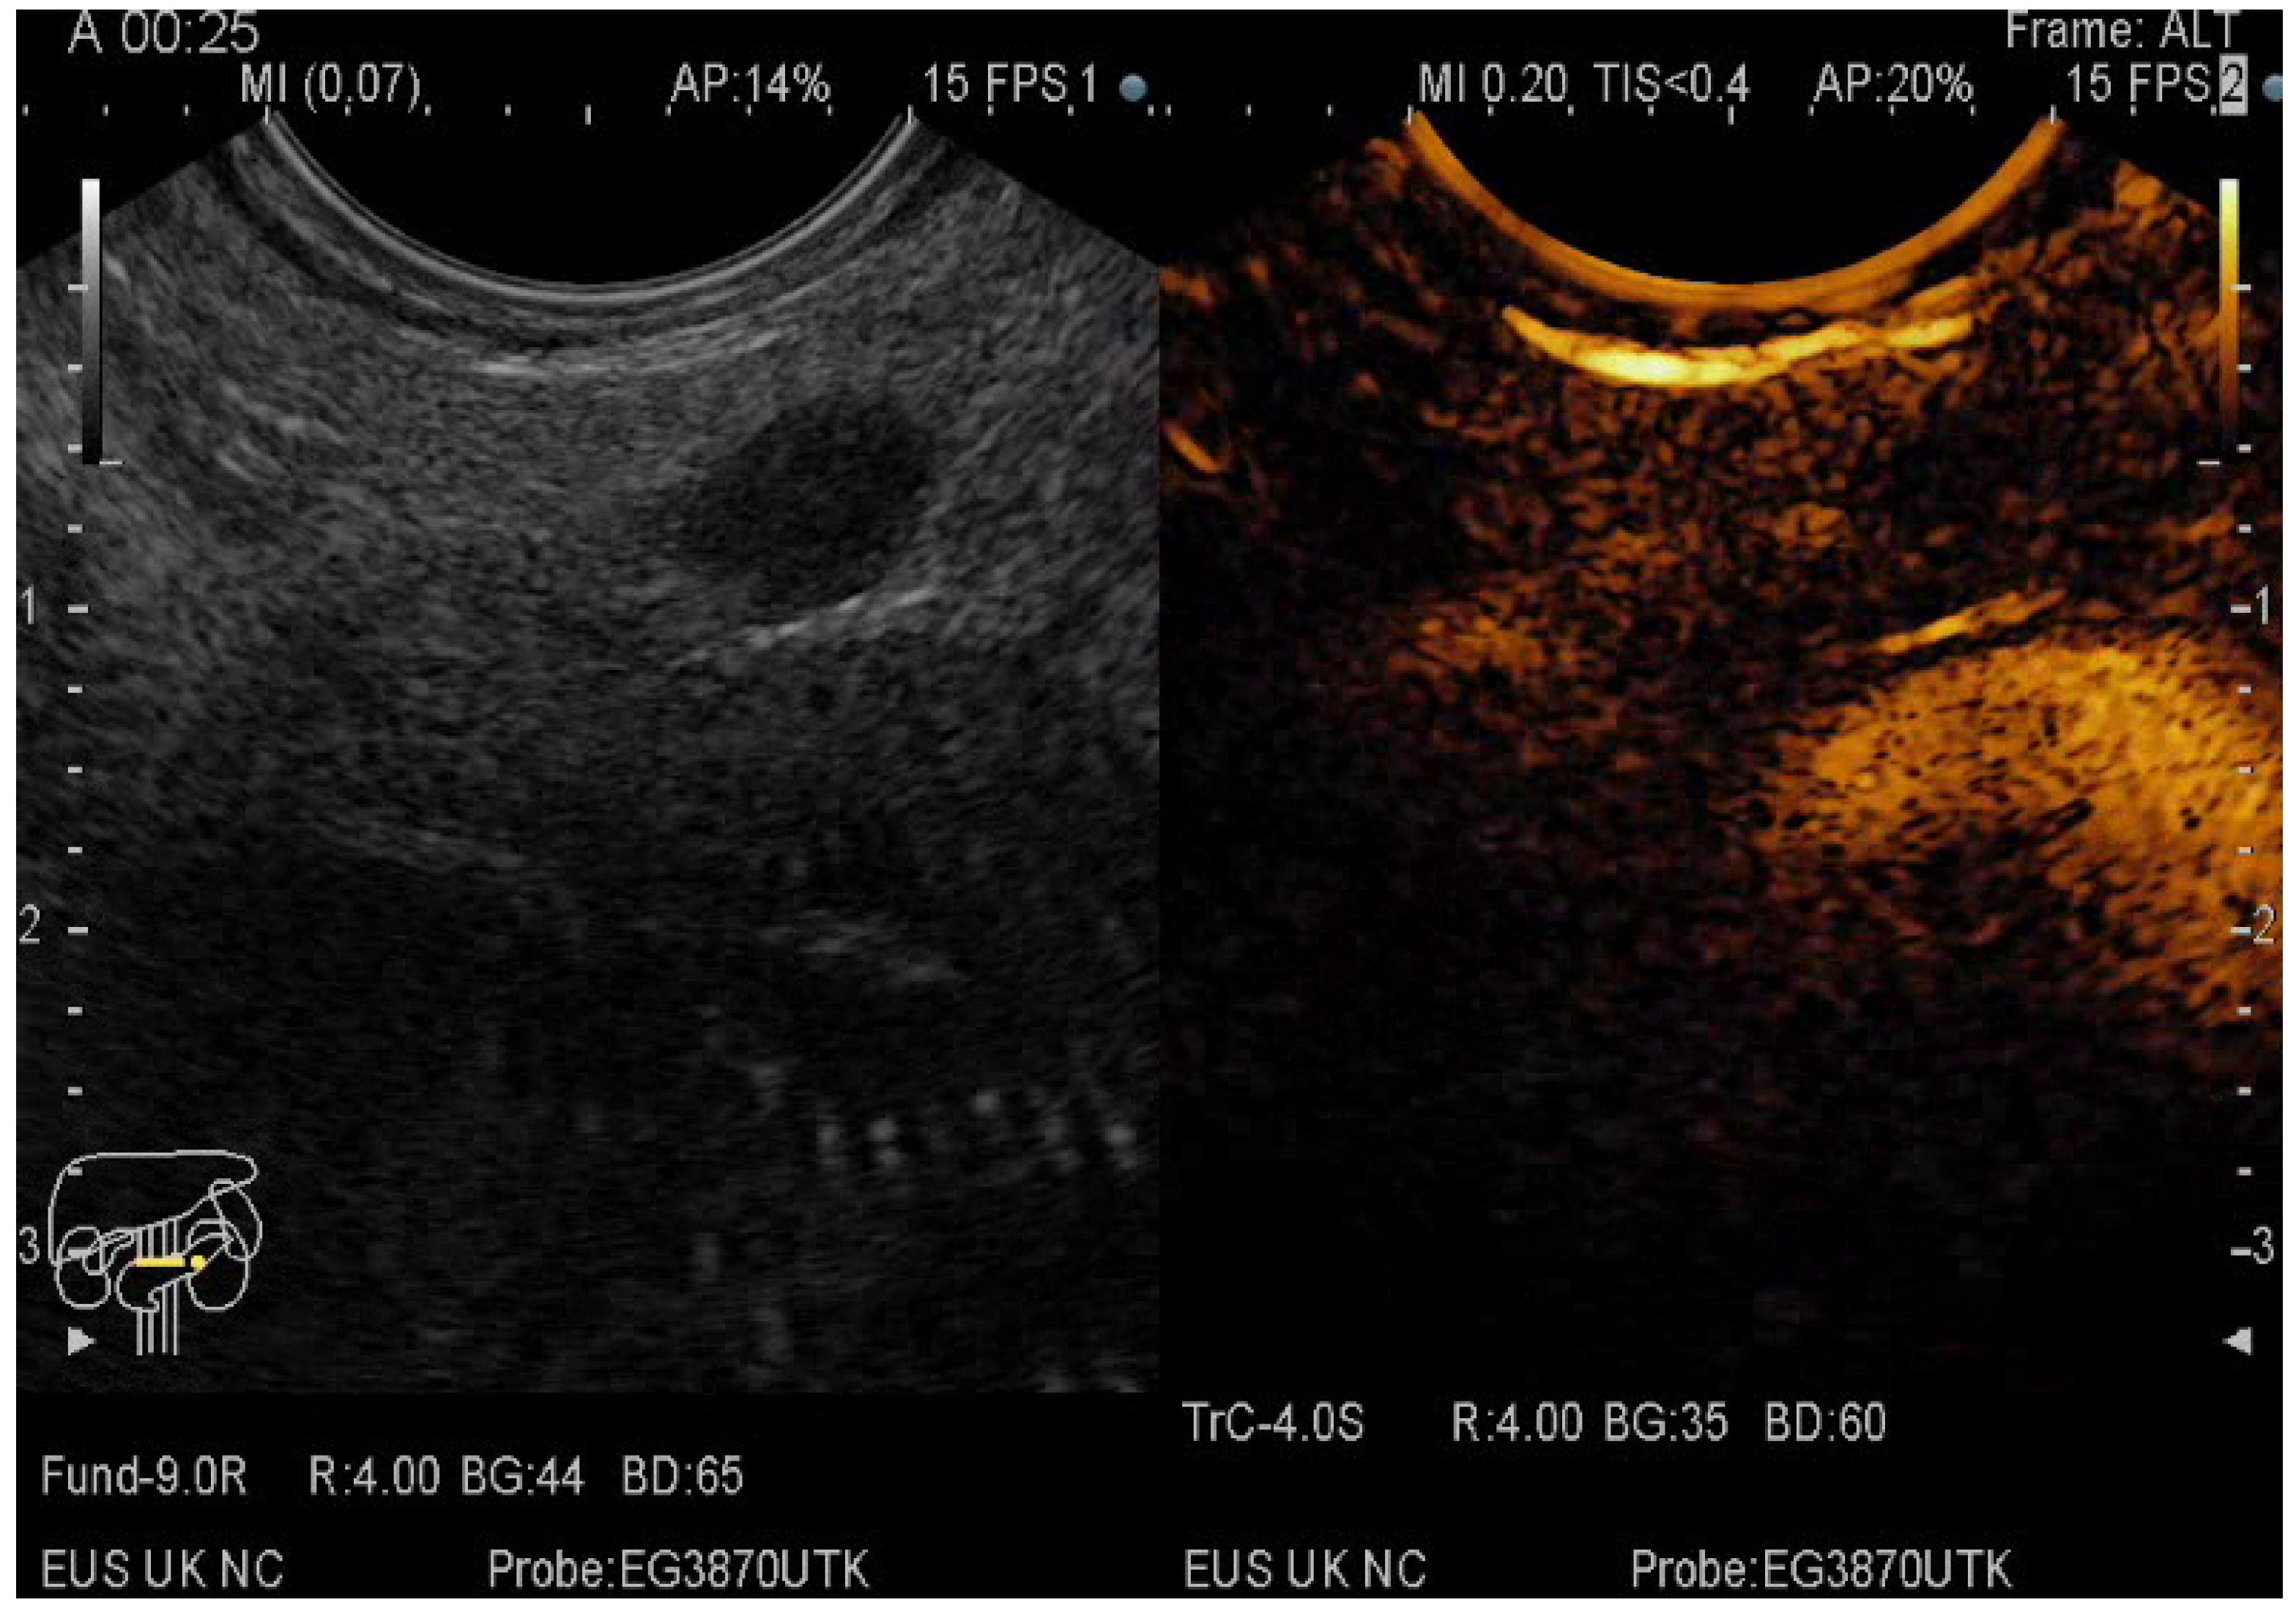

2.5. CE-EUS Procedure

- the entanglement of CE-EUS in describing pseudocysts and the benign/premalignant/malignant character of pancreatic cystic lesions

3.3. EUS-FNA/FNB + CE-EUS of Pancreatic Cystic Lesions Subgroup